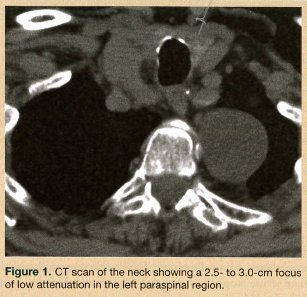

On physical examination, the patient had a body mass index of 22.4. She was hemodynamically stable and well oriented, with no evidence of neurological deficit. Her oropharynx was clear and her uvula was erythematous. Saliva drooled from the angle of mouth, with no clinical suggestion of aspiration. An attempted upper esophageal endoscopy revealed obstruction of the upper esophagus and blackish discoloration of the esophageal mucosa, and it could not be completed. A chest radiograph and electrocardiogram were unremarkable. Fiberoptic laryngoscopy ruled out an upper airway lesion, but showed posterior glottic edema. Computed tomography (CT) scans of the neck and chest added to the confusion, showing a soft-tissue density surrounding the proximal esophagus and a possible 2.5-cm homogenous attenuated paraspinal density (most likely a nerve sheath tumor) in the left upper lobe (Figure 1). A barium swallow esophagram was performed, which showed the esophagus being compressed by the mass (Figure 2). Magnetic resonance imaging of the patient’s head and neck revealed a circumferential mass lesion around the proximal esophagus and a left paraspinal round, well-circumscribed area representing a mass or complex cyst.